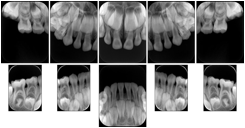

Intra-oral radiography typically involves acquisition of multiple images of various parts of the dentition. Many digital radiographic systems offer customized templates that are used for displaying the images in a study on the screen. These templates may also be referred to as mounts or view sets. The Structured Display Object represents a standard method of encoding and exchanging the layout and intended display of Structured Displays. A structured display object created in this manner could be stored with a study and exchanged with images to allow for complete reproduction of the original exam.

3. A dental provider wishes to capture a series of DICOM IO images for the patient’s dentition. The tooth morphology, teeth are divided into molars, premolars, canines and incisors, and a number of images for each jaw. The anatomic information was captured utilizing the triplet of schema. This standard code sequence is based on ISO 3950-2010, Dentistry - Designation system for teeth and areas of the oral cavity.

In most standard cases, images are oriented in structured layouts. These structured displays are useful to be shared between providers for reference purposes.